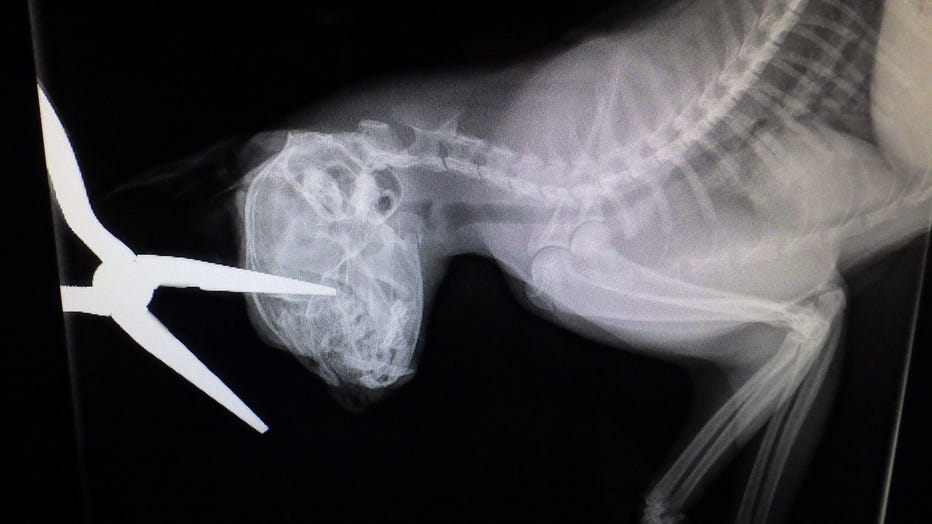

A cat was stabbed in the head with pliers and officers want to know who did it. (Credit: Indianapolis Animal Care Services)

An X-ray after a cat is stabbed in the head with pliers. (Credit: Indianapolis Animal Care Services)